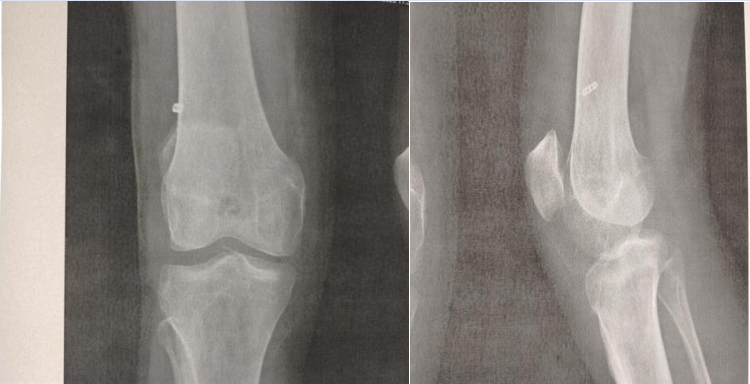

This is a retrospective study that involved 40 patients whose average age was 35 years (with extremes of 18 to 45 years) with a male predominance of 90% . The initial trauma was a sport accident in 70% of cases, a road accident in 20% and a work accident in 10% . The mechanism of injury frequently encountered was a flexion external rotation valgus in 40.7% of cases The left knee was still the most affected (60%). Subjective and objective laxity was present for all patients with a positive Lachmann and anterior drawer test for all patients MRI showed total interstitial ACL rupture in all patients, associated with meniscal lesions for 10 patients, he femoral fixation (fig 01) was made by an endobutton, in the tibial the fixation was ensured by an absorbable interference screw. The mean overall preoperative score according to Lysholm fell from 66.5 to 87 postoperatively. With an average follow-up of 24 months, the overall results were evaluated according to the IKDC score, they were excellent and good in 87% of cases. with a satisfactory reduction in pain and a resumption of usual sports activity 9 months after surgery. 40% of our sports patients have recovered to a level similar to that before the trauma. No immediate postoperative complications were noted to our patients.